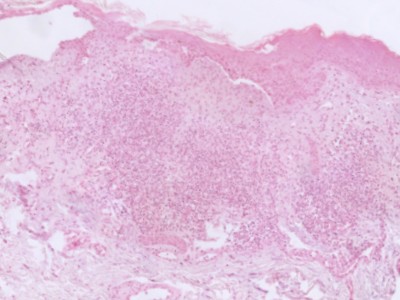

Groeiwijzen (histologische

varianten):Naast klinische varianten worden er ook histologische

varianten onderscheiden. Binnen 1 laesie kunnen verschillende groeiwijzen gecombineerd

voorkomen, een biopt kan niet representatief zijn voor de hele laesie. Sprieterige

en micronodulaire BCC's zijn agressiever dan compacte of superficiële BCC's.

| 1. |

compact basaalcelcarcinoom (solide, nodulair). Er zijn grote

nesten met duidelijke begrenzing naar het omgevende niet-aangedane

weefsel. De stromareactie is vaak beperkt. |

| 2. |

superficieel basaalcelcarcinoom, zeer oppervlakkige nesten,

vaak multifocaal. |

| 3. |

sprieterig basaalcelcarcinoom, kleine strengetjes van basaloïde

cellen omgeven door desmoplastisch stroma, de begrenzing naar het

omgevende weefsel is vaak onscherp. |

| 4. |

micronodulair basaalcelcarcinoom, groeiend in kleine, fraai

afgeronde nesten elk ongeveer ter grootte van de bulbus van een

haarfollikel. |